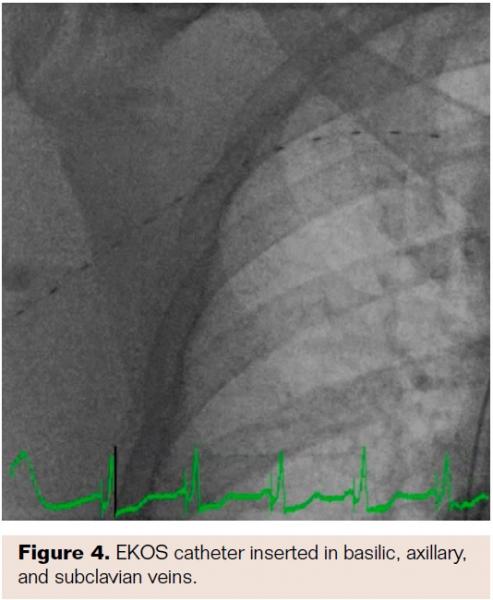

Subsequently, the PICC line was accessed with insertion of a 0.014˝ wire which was advanced into the right atrium. The PICC line was then removed, and a 6 Fr glidesheath inserted into the basilic vein over the 0.014˝ wire. A venogram demonstrated complete occlusion of the brachial and basilic veins (Figure 3). The Angiojet Peripheral Thrombectomy Catheter (Boston Scientific) was initially used for thrombectomy in the right axillary and subclavian veins with minimal debris removed. Ensuing venogram showed no improvement of venous flow. Therefore, an EKOS Catheter (BTG) with a 30 cm treatment length was inserted into the right basilic, axillary, and subclavian veins (Figure 4). Alteplase infusion at 1 mg per hour, and heparin infusion at 500 units per hour, was initiated for a total of 12 hours. The patient was transferred to the medical intensive care unit for observation.